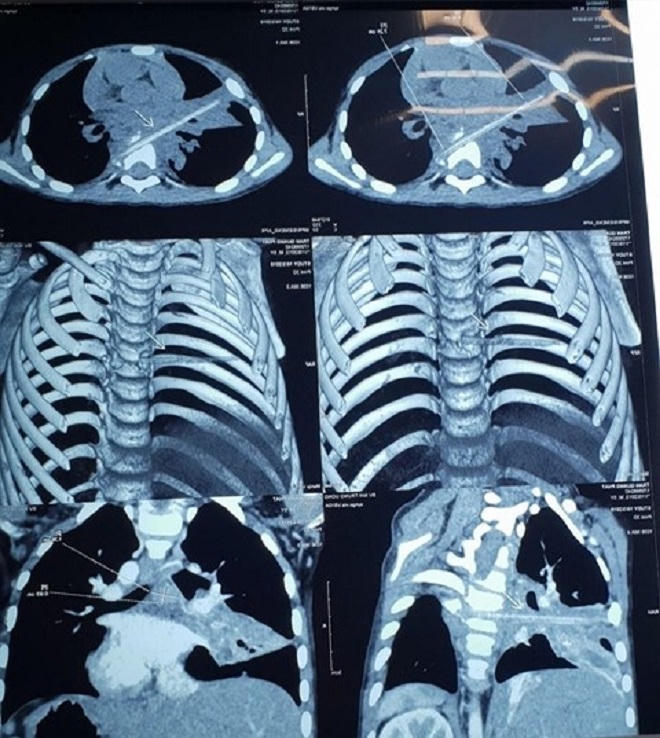

Đến ngày 3/10, khi thấy con có biểu hiện giống hai lần trước đó, gia đình đã chuyển bé trai đến bệnh viện Nhi Trung ương. Bé M được đưa chụp cắt lớp vi tính, các bác sĩ phát hiện một dị vật dài nhọn kích thước 72x4mm tại vị trí nhu mô thùy phổi ở thùy giữa phổi phải.

Dị vật này đi từ trước ra sau, xuyên qua khe giữa 2 thân đốt sống 6, 7 và làm vỡ thân đốt sống. Khi nằm lại trong cơ thể, dị vật gây phản ứng thâm nhiễm viêm trung thất sau quanh đốt sống 6,7. Đây cũng chính là nguyên nhân khiến cháu M phải vào viện vì viêm phổi trong suốt 8 tháng.